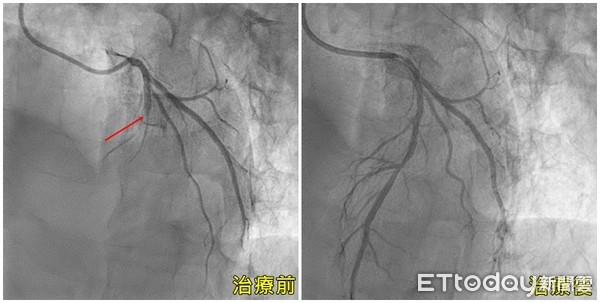

亞洲大學附屬醫院心導管室主任黃國書表示,陳先生送到急診室後,又經過CPR及電擊兩次後,才恢復心跳,經心導管檢查確診為心肌梗塞所致,並緊急打通血管,但因患者仍意識昏迷,術後於加護病房接受24小時低溫治療,陳先生不但撿回一命,更幸運能夠順利恢復意識,且迄今無明顯的神經學後遺症,在臨床上實屬相當不易。